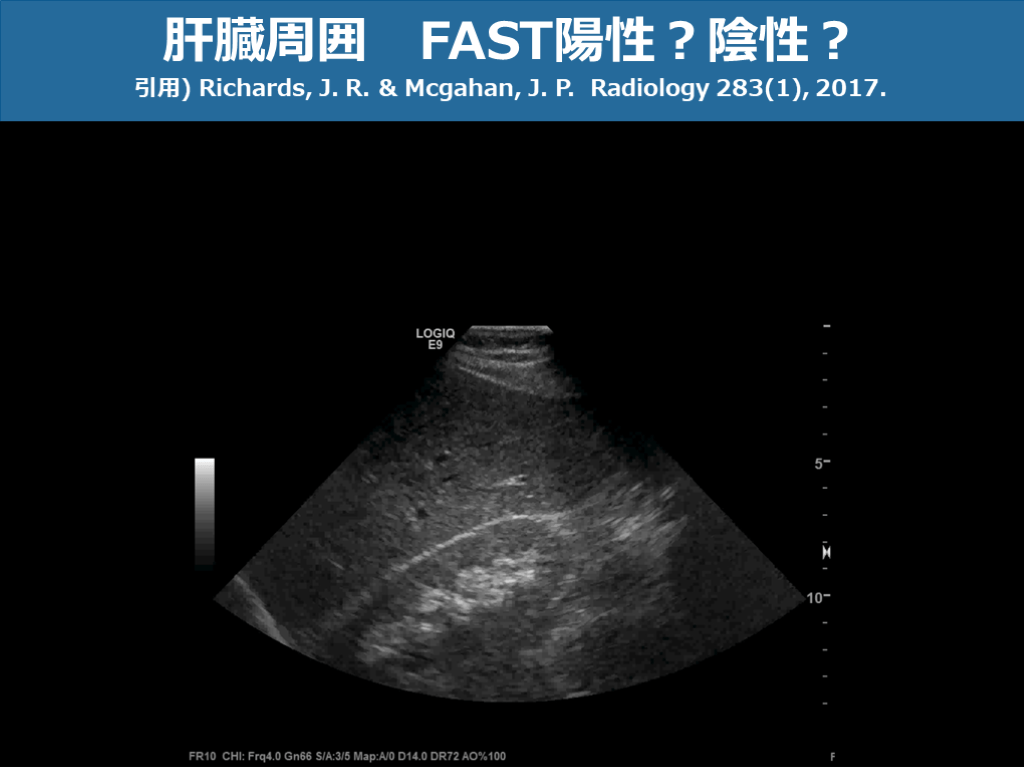

肝臓周囲 FAST陽性?陰性? 引用) Richards, J. R. & Mcgahan, J. P. Radiology 283(1), 2017. スライド画像)広島大学病院 演者作成

肝臓周囲 FAST陽性?陰性? 引用) Richards, J. R. & Mcgahan, J. P. Radiology 283(1), 2017. スライド画像)広島大学病院 演者作成 モリソン窩少量EFSあり

肝臓周囲 FAST陽性?陰性? 引用) Richards, J. R. & Mcgahan, J. P. Radiology 283(1), 2017. スライド画像)広島大学病院 演者作成 肝臓周囲 正常所見

肝臓周囲 FAST陽性?陰性? 引用) Richards, J. R. & Mcgahan, J. P. Radiology 283(1), 2017. スライド画像)広島大学病院 演者作成 肝損傷+血腫を伴う液体貯留あり